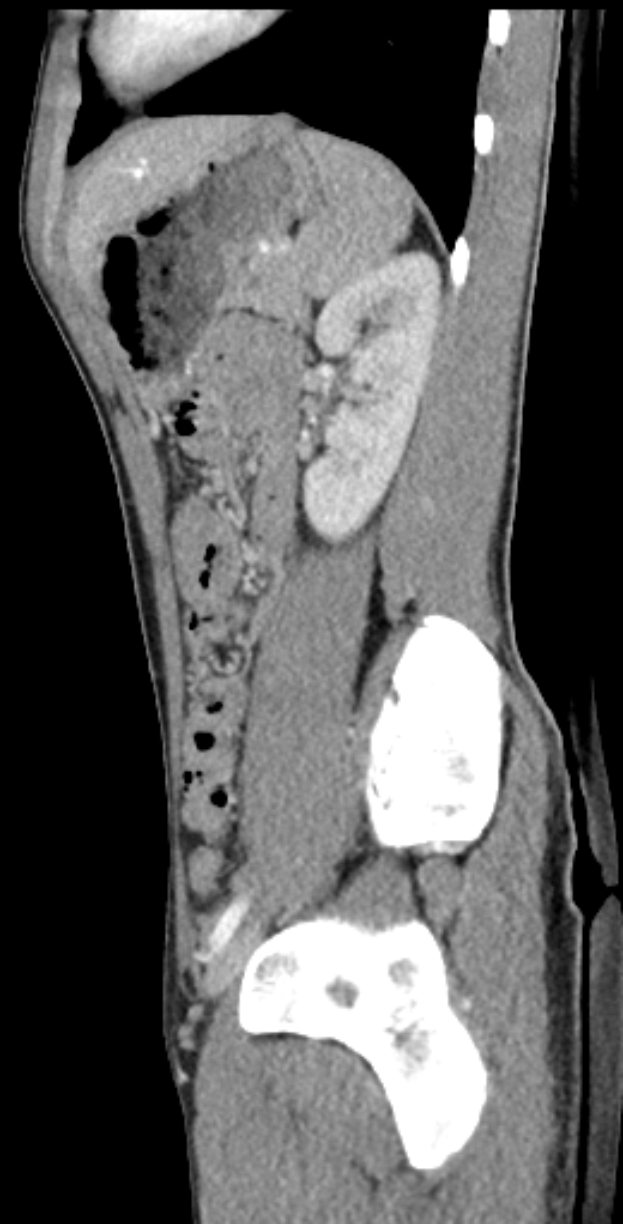

Eine MRT-Aufnahme eines Knies, die einen Bruch in der Mitte zeigt, umgeben von einem dunklen Hintergrund.Juan Adler

Der 1. FC Köln hat zwei Leistungsträger durch Muskelverletzungen verloren. Sowohl Jan Thielmann als auch Sebastian Sebulonsen fielen nach MRT-Untersuchungen, die die Verletzungen bestätigten, vorerst aus. Der Rückschlag kommt nach dem jüngsten Spiel der Mannschaft gegen die TSG Hoffenheim.

Thielmann verletzte sich bereits beim Aufwärmen vor dem Hoffenheim-Spiel und konnte daher nicht am Match teilnehmen. Sebulonsen begann zwar die Partie, musste aber in der 69. Minute verletzt vom Platz.

Die medizinische Abteilung führte bei beiden Spielern MRT-Untersuchungen durch, die die Muskelverletzungen bestätigten. Beide fallen damit vorerst aus.